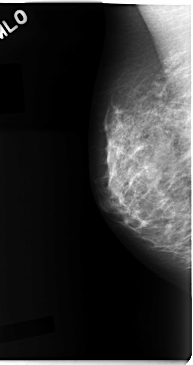

C_0090_1.LEFT_MLO

LEFT_MLO LINES 4688 PIXELS_PER_LINE 2568 BITS_PER_PIXEL 12 RESOLUTION 50 OVERLAY